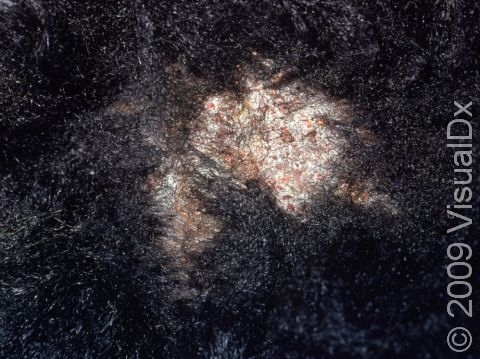

Ringworm, Scalp (Tinea Capitis)

Scalp ringworm appears as one or more round to oval areas covered with gray scale and is often associated with hair loss. The patches may be red and inflamed, and small pus-filled bumps (pustules) may sometimes be found. Also seen on the surface of the scalp may be tiny black dots, which represent broken hairs.

One complication of scalp ringworm is a kerion, a large, oozing, pus-filled lump. If not treated aggressively, a kerion can lead to scarring and permanent hair loss.